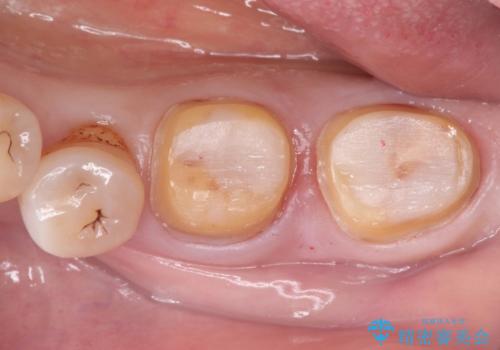

咬合が強く、歯牙にマイクロクラックが入っている状態でした。歯髄は保存可能と診断され、フルジルコニアクラウンによる治療を行いました。

咬合面に広範囲の修復物がある状態で中心に強い力が加わると歯牙は外方性の歪みが生じ、マイクロクラックができます。これを防ぐには、咬頭被覆するアンレー、もしくはクラウンによる治療が必要です。